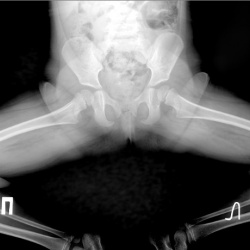

Уважаемые коллеги, есть ли перелом? Молодая девушка, 2 дня назад упала на ягодицы

Пациентка 55 лет. В гололёд падение на борбдюр областью кочика.